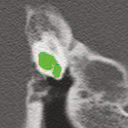

Deep learning based medical image segmentation models usually require large datasets with high-quality dense segmentations to train, which are very time-consuming and expensive to prepare. One way to tackle this challenge is by using the mixed-supervised learning framework, in which only a part of data is densely annotated with segmentation label and the rest is weakly labeled with bounding boxes. The model is trained jointly in a multi-task learning setting. In this paper, we propose Mixed-Supervised Dual-Network (MSDN), a novel architecture which consists of two separate networks for the detection and segmentation tasks respectively, and a series of connection modules between the layers of the two networks. These connection modules are used to transfer useful information from the auxiliary detection task to help the segmentation task. We propose to use a recent technique called "Squeeze and Excitation" in the connection module to boost the transfer. We conduct experiments on two medical image segmentation datasets. The proposed MSDN model outperforms multiple baselines.